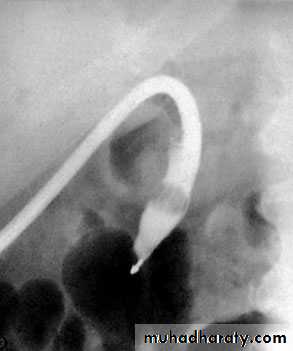

51NORMAL ERCP

Al-Madena copy

52